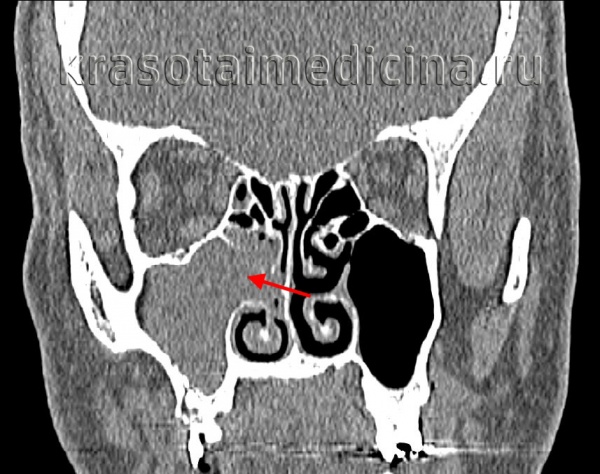

(Слева) При корональной «костной» КТ определяется снижение пневматизации левой верхнечелюстной пазухи, устье которой расширено. Визуализируется большой одиночный полип, пролабирующий через устье в полость носа и приводящий к обструкции среднего носового хода.